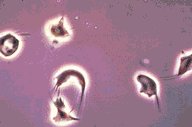

Sickle cell anemia

This low oil magnification is of a polarized phase microscopic

view of permanently sickled cells.